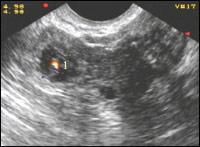

| Рисунок 13

| Эффективность допплерографии Перед нами оптимальный клинический вариант, демонстрирующий плюсы метода.

| Рисунок 14

| Цветовая допплерография внематочной беременности Развивающаяся внематочная беременность. Цветовые пятна отражают кровообращение эмбриона (1) и в эктопически расположенном трофобласте (2)

| Рисунок 15

| Цветовая допплерография внематочной беременности Развивающаяся внематочная беременность. Цветовые пятна отражают кровообращение эмбриона (1)

Используя методику цветового картирования, в придатковом образовании определяется зона гиперваскуляризации, которая представляет собой трофобластический кровоток, отражающий интенсивное кровоснабжение эктопического эмбриона. Частота определения кровотока составляет 80-92 % случаев. Отсутствие визуализации трофобластического кровотока наблюдается при диаметре плодного яйца менее 10 мм или при прерывании беременности в малом сроке. По мере роста плодного яйца и пенетрации ворсин хориона в стенку маточной трубы начинает регистрироваться периферический кровоток с нарастающей интенсивностью, а в акушерском сроке беременности более 6 недель, имеется замкнутое кольцо из цветовых локусов.

Трофобластический артериальный кровоток при прогрессирующей трубной беременности характеризуется высокой конечно-диастолической скоростью, при этом отмечается низкорезистентный тип кривой скорости кровотока с тенденцией снижения численных значений ИР по мере увеличения срока беременности, показатели которых составляют 0,35-0,53.